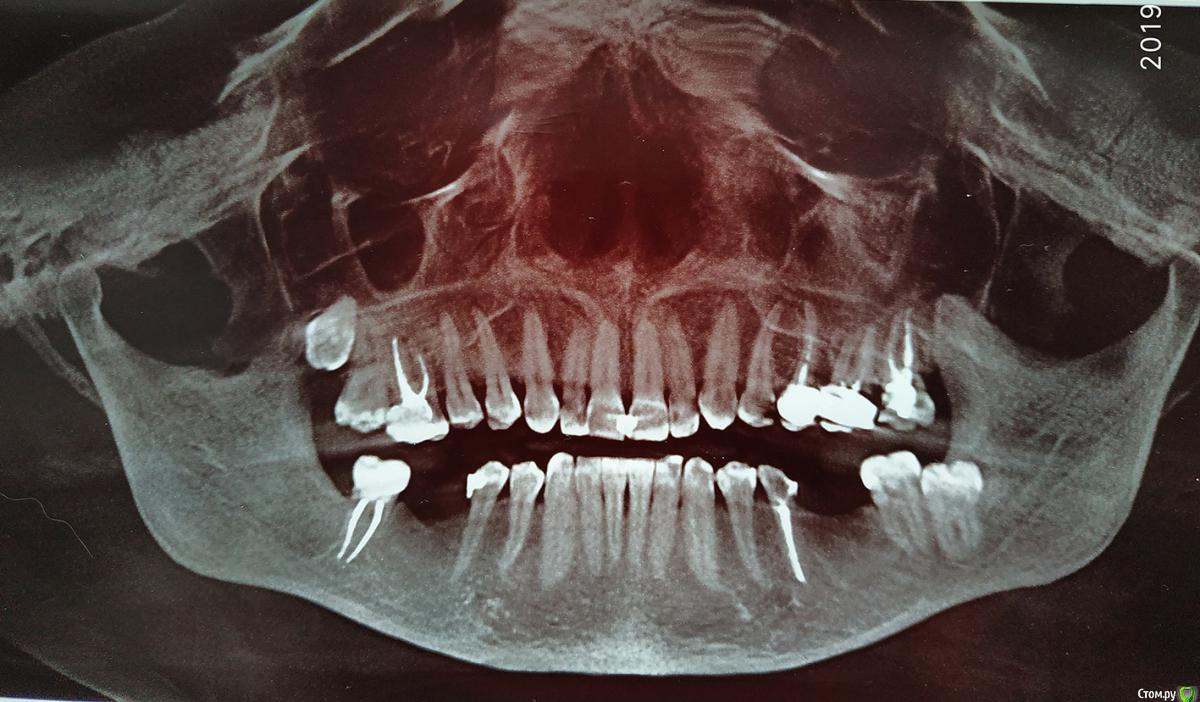

arinasmirn74@gmail.com Опубликовано 2 августа, 2019 Автор Поделиться Опубликовано 2 августа, 2019 (изменено) Ситуация до имплантации и после. Второй снимок в Пикассо фиговый, попробую переделать, но может быть что-то и понятно. Изменено 2 августа, 2019 пользователем arinasmirn74@gmail.com Ссылка на комментарий